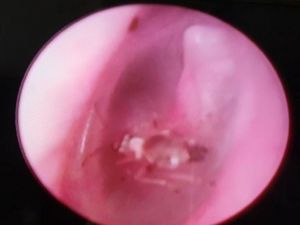

Kulağından canlı sinek çıktı